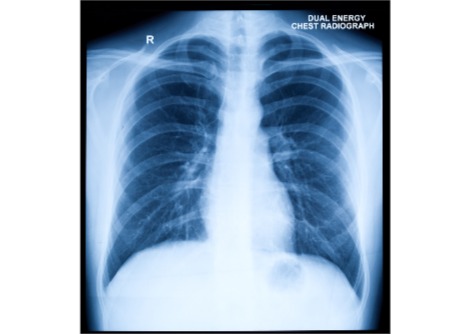

يقترح الباحثون أن طريقتهم يُمكن استخدامها في البيئات السريرية لتحديد الأشخاص المعرضين لخطر السقوط بشكل أفضل. وبينما لا تزال هذه التقنية بحاجة إلى مزيد من التحسين، أوضح تينغ: "قد نتمكن من تحديد ما إذا كان لدى شخص ما نشاط دماغي متزايد بمجرد تقييم النشاط العضلي بعد فقدان التوازن".

إذا تم التحقق من صحة هذا النهج، فإنه قد يساعد في اكتشاف مشاكل التوازن مبكراً، مما يسمح للأفراد المعرضين للخطر بالاستفادة من التدريب والتمارين المستهدفة قبل حدوث السقوط.